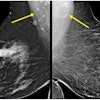

An AI model developed by a team of researchers from China can differentiate between benign and malignant breast microcalcifications, according to findings published June 18 in Fundamental Research.

A team led by doctoral candidate Qing Lin from Fudan University in Shanghai reported that their model showed high-performance metrics when evaluating microcalcifications on mammograms, which could translate to the technology being used as an adjunct reader.

Lin and colleagues developed a machine learning model that focuses on interpreting breast microcalcifications. To do so, they used an algorithm to find pixels from calcification regions. They also used a feature pyramid network to treat all the feature layers at different scales since calcification regions are usually small.

Using images from multiple health centers, the researchers collected data from 4,810 mammograms with 6,663 microcalcification lesions confirmed on biopsy. Of these, 3,301 were deemed to be malignant while 3,362 were benign.

The researchers found overall moderate to high classification values in training and test sets for differentiating between benign and malignant breast microcalcifications. These included high accuracy and area under the curve (AUC) values.